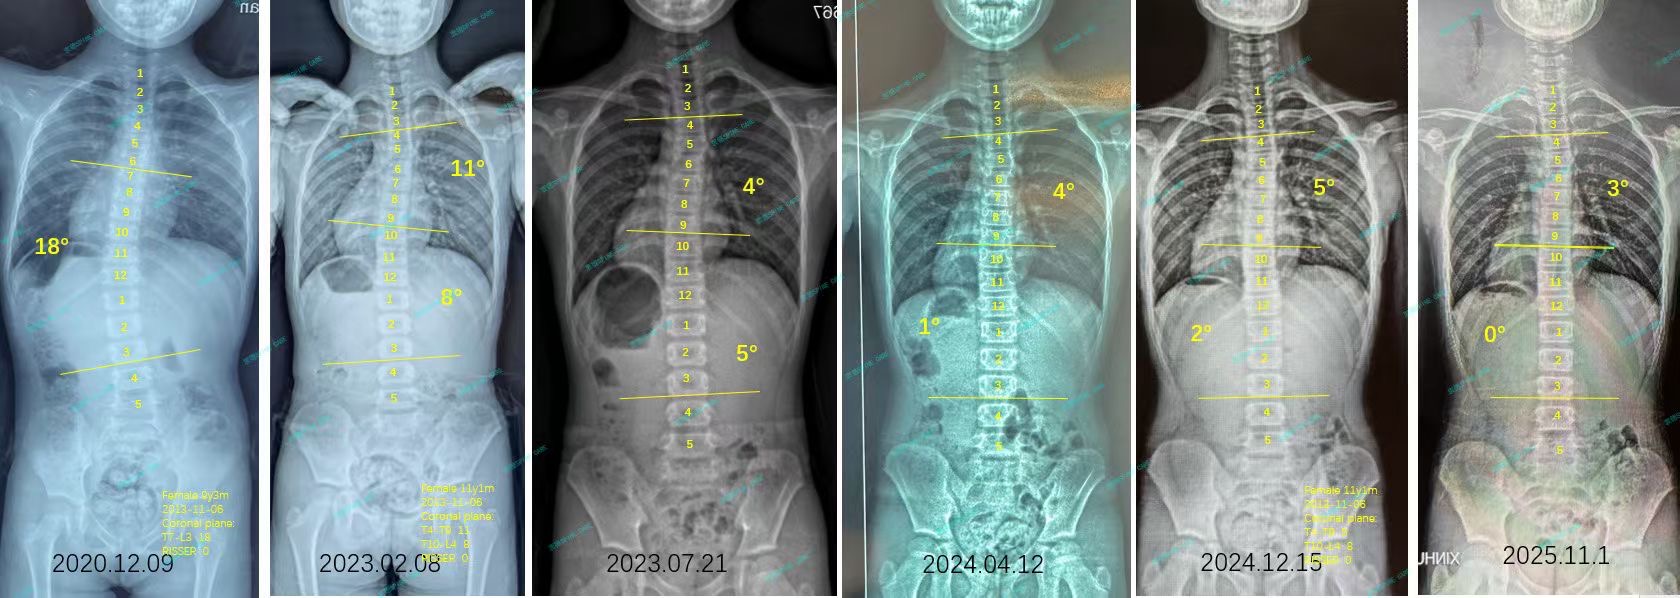

来自家长对衷德的评价(娴娴妈妈)